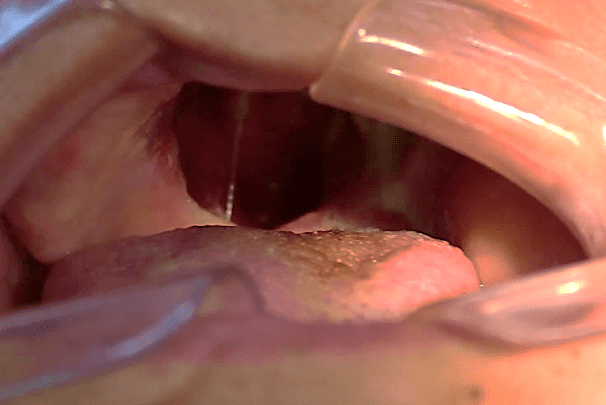

A 49-year-old female patient attended the prosthesis clinic at Nilton Lins University, mentioning dissatisfaction with her total obturator prosthesis, because she had a “broken front tooth” and the prosthesis was “falling”, emphasizing the desire to maintain the shape of the same. In the anamnesis reported that previously in 2012 he was diagnosed with mucoepidermoid carcinoma of intermediate degree in the palate (Appendix 1) and in 2013 after performing surgical removal and performing new tests, who did not indicate the presence of malignancy (Appendix 2), was attested as cured, besides being hypertensive and using the drugs losartan potassium 50 mg twice daily and levanlodipine besidate 2.5 mg once a day. No alterations were observed on extraoral clinical examination. In the intraoral clinical examination, there was absence of the upper arch teeth, bucosinusal communication and partial maxillary edge and in the lower region only the presence of teeth 31, 32, 33, 41, 42, 43, 44 and 45 (figures 1 and 2).

Figure 2: Initial aspect of the patient in occlusion.

Continuing, the last molding of the clone’s test base with fluid condensation silicone (Oranwash L®, Zhermack, Italy) (figures 18 and 19) was made, and the patient remained with the teeth in occlusion for molding (closed mouth technique). The test bases and molding were forwarded to acrilization.

After acrilization of the obturator prosthesis, it was installed in order to verify the necessary adjustments still with the PPR test base, with no need for adjustments (figure 20). The PPR was sent for acrylization and at the end the prostheses were installed checking the adjustments again, verifying favorable adaptation, reestablishing comfort, function and aesthetics for the patient (figure 21).

Figure 20: Proof of the obturator prosthesis after acryllization based on the PPR test.

Figure 21: Final aspect.